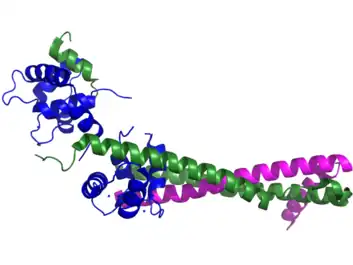

Cardiac troponin I, often denoted as cTnI, is presented in cardiac muscle tissue by a single isoform with a molecular weight of 23.9 kDa. It consists of 209 amino acid residues. The theoretical pI of cTnI is 9.05.[4] cTnI differs from other troponins due to its N-terminal extension of 26 amino acids. This extension contains two serines, residues 23 and 24, which are phosphorylated by protein kinase A in response to beta-adrenergic stimulation and important in increasing the inotropic response.[5] Phosphorylation of cTnI changes the conformation of the protein and modifies its interaction with other troponins as well as the interaction with anti-TnI antibodies. These changes alter the myofilament response to calcium, and are of interest in targeting heart failure. Multiple reaction monitoring of human cTnI has revealed that there are 14 phosphorylation sites and the pattern of phosphorylation observed at these sites is changed in response to disease.[6] cTnI has been shown to be phosphorylated by protein kinase A, protein kinase C, protein kinase G, and p21-activated kinase 3.[7]

- ↑ Takeda, Soichi; Yamashita, Atsuko; Maeda, Kayo; Maéda, Yuichiro (July 2003). "Structure of the core domain of human cardiac troponin in the Ca2+-saturated form". Nature. 424 (6944): 35–41. Bibcode:2003Natur.424...35T. doi:10.1038/nature01780. ISSN 1476-4687. PMID 12840750. S2CID 2174019.